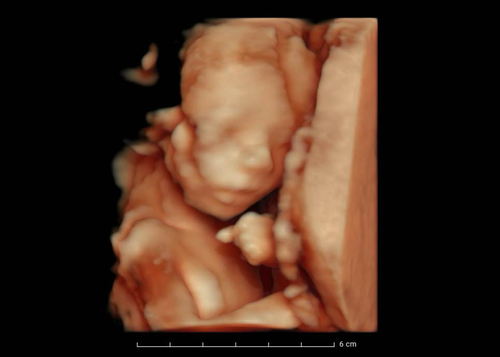

Wat ik heb gehoord is dat het het leukste is om tussen de 24 en 31 weken een 3D/4D echo te maken❤️ Ik heb een afspraak gemaakt voor week 27

Wij hebben het bij de eerste met 26 weken gedaan, dit was echt perfect, heel mooi beeld. Hoe later je gaat hoe minder mooi beeld je krijgt omdat je kindje steeds groter wordt en er minder ruimte is in je baarmoeder om te draaien etc. (Is mij verteld) maar je kan altijd bij een echopraktijk informeren

Wij twijfelen ook nog wanneer we pretecho gaan laten doen. Ik denk tussen week 28 en 30 hoor vaak dat je dan hele mooie beelden hebt. Tenminste als je baby’tje een beetje goed ligt 😁 wij hadden vandaag 20 weken echo en ik kreeg daar onverwachts ook een 3D beeld bij ik had niet verwacht dat het al zo een mooi beeld zou zijn.

Mijn gynaecoloog laat de baby bij elke echo (om de 4 weken) even in 3D zien. Hoe vroeger in de zwangerschap, hoe 'vollediger' je hem/haar in beeld krijgt. Tijdens mijn eerste zwangerschap hebben we het mooiste beeld kunnen krijgen met 24 weken. Toen had hij nog best veel plek om te bewegen en hadden we echt een zuiver beeld. Verder in de zwangerschap vallen er (naar onze ervaring) meer stukjes van het gezicht weg doordat het wat krapper is in de baarmoeder.